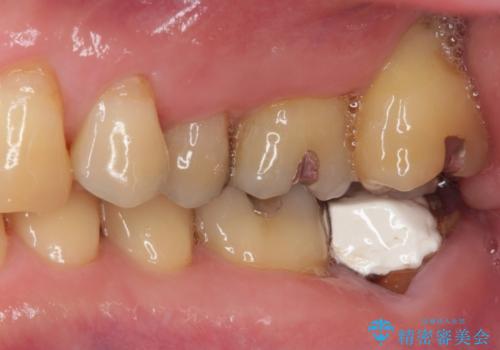

上顎左右の歯をアンカースクリューを用いた部分矯正により位置を修正し、オールセラミッククラウンにて補綴治療を行うこととしました。

矯正治療に時間はかかりましたが、外側に飛び出した歯が内側に収まったことで、非常に歯が磨きやすくなったとのことでした。